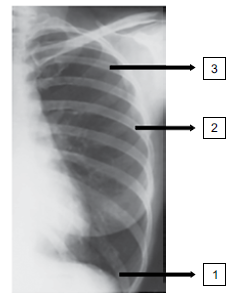

Observe a imagem a seguir:

Assinale a alternativa que corresponde às estruturas assinaladas na imagem.